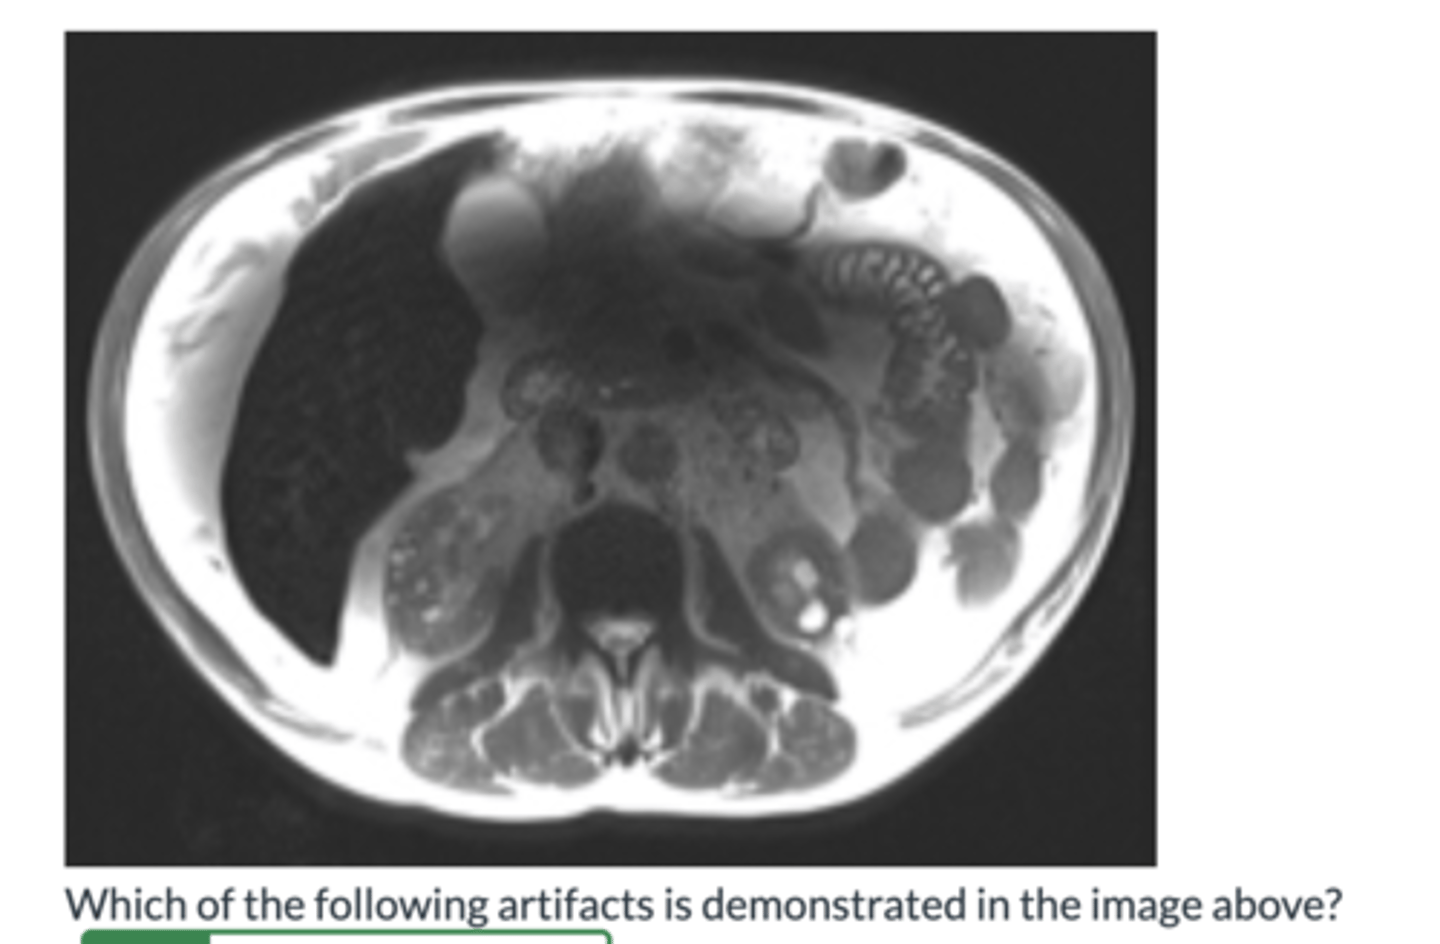

Aliasing/Wrap Artifact

Phase Mismapping Artifact

Dielectric Artifact